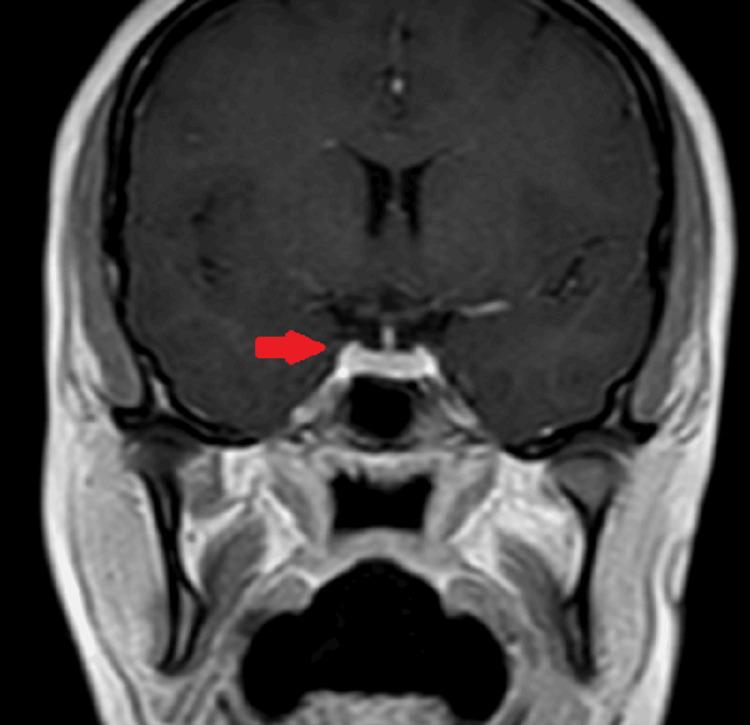

Pituitary lesions can occur as a consequence of primary hypothyroidism and the biochemical imbalance associated with it, making its diagnosis a challenging task necessitating a thorough patient assessment by the treating physicians. We describe a young patient with pituitary hyperplasia due to primary hypothyroidism who presented with complaints of menstrual irregularities and weight gain. The patient was treated with thyroxine (T4) for primary hypothyroidism. The patient reported improvement in her symptoms along with the normalization of thyroid profile and interval reduction in the size of pituitary lesion on follow-up MRI scan.

垂体病变可能是原发性甲状腺功能减退及其相关生化失衡的结果,这使得其诊断成为一项具有挑战性的任务,需要治疗医生对患者进行全面评估。我们描述了一名因原发性甲状腺功能减退导致垂体增生的年轻患者,她出现月经不规律和体重增加的症状。该患者接受了甲状腺素(T4)治疗原发性甲状腺功能减退。患者报告症状有所改善,甲状腺指标恢复正常,随访磁共振成像扫描显示垂体病变大小逐渐缩小。